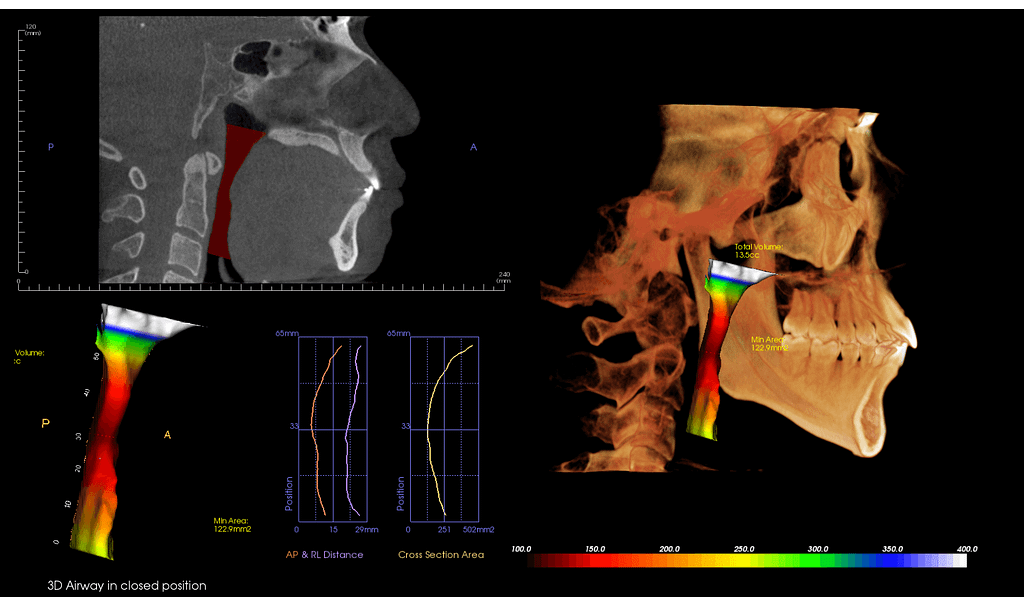

Airway Scan

The upper airway is an extraordinarily complex anatomic region that may be affected by various disease states. The upper airway includes the nose, nasopharynx,